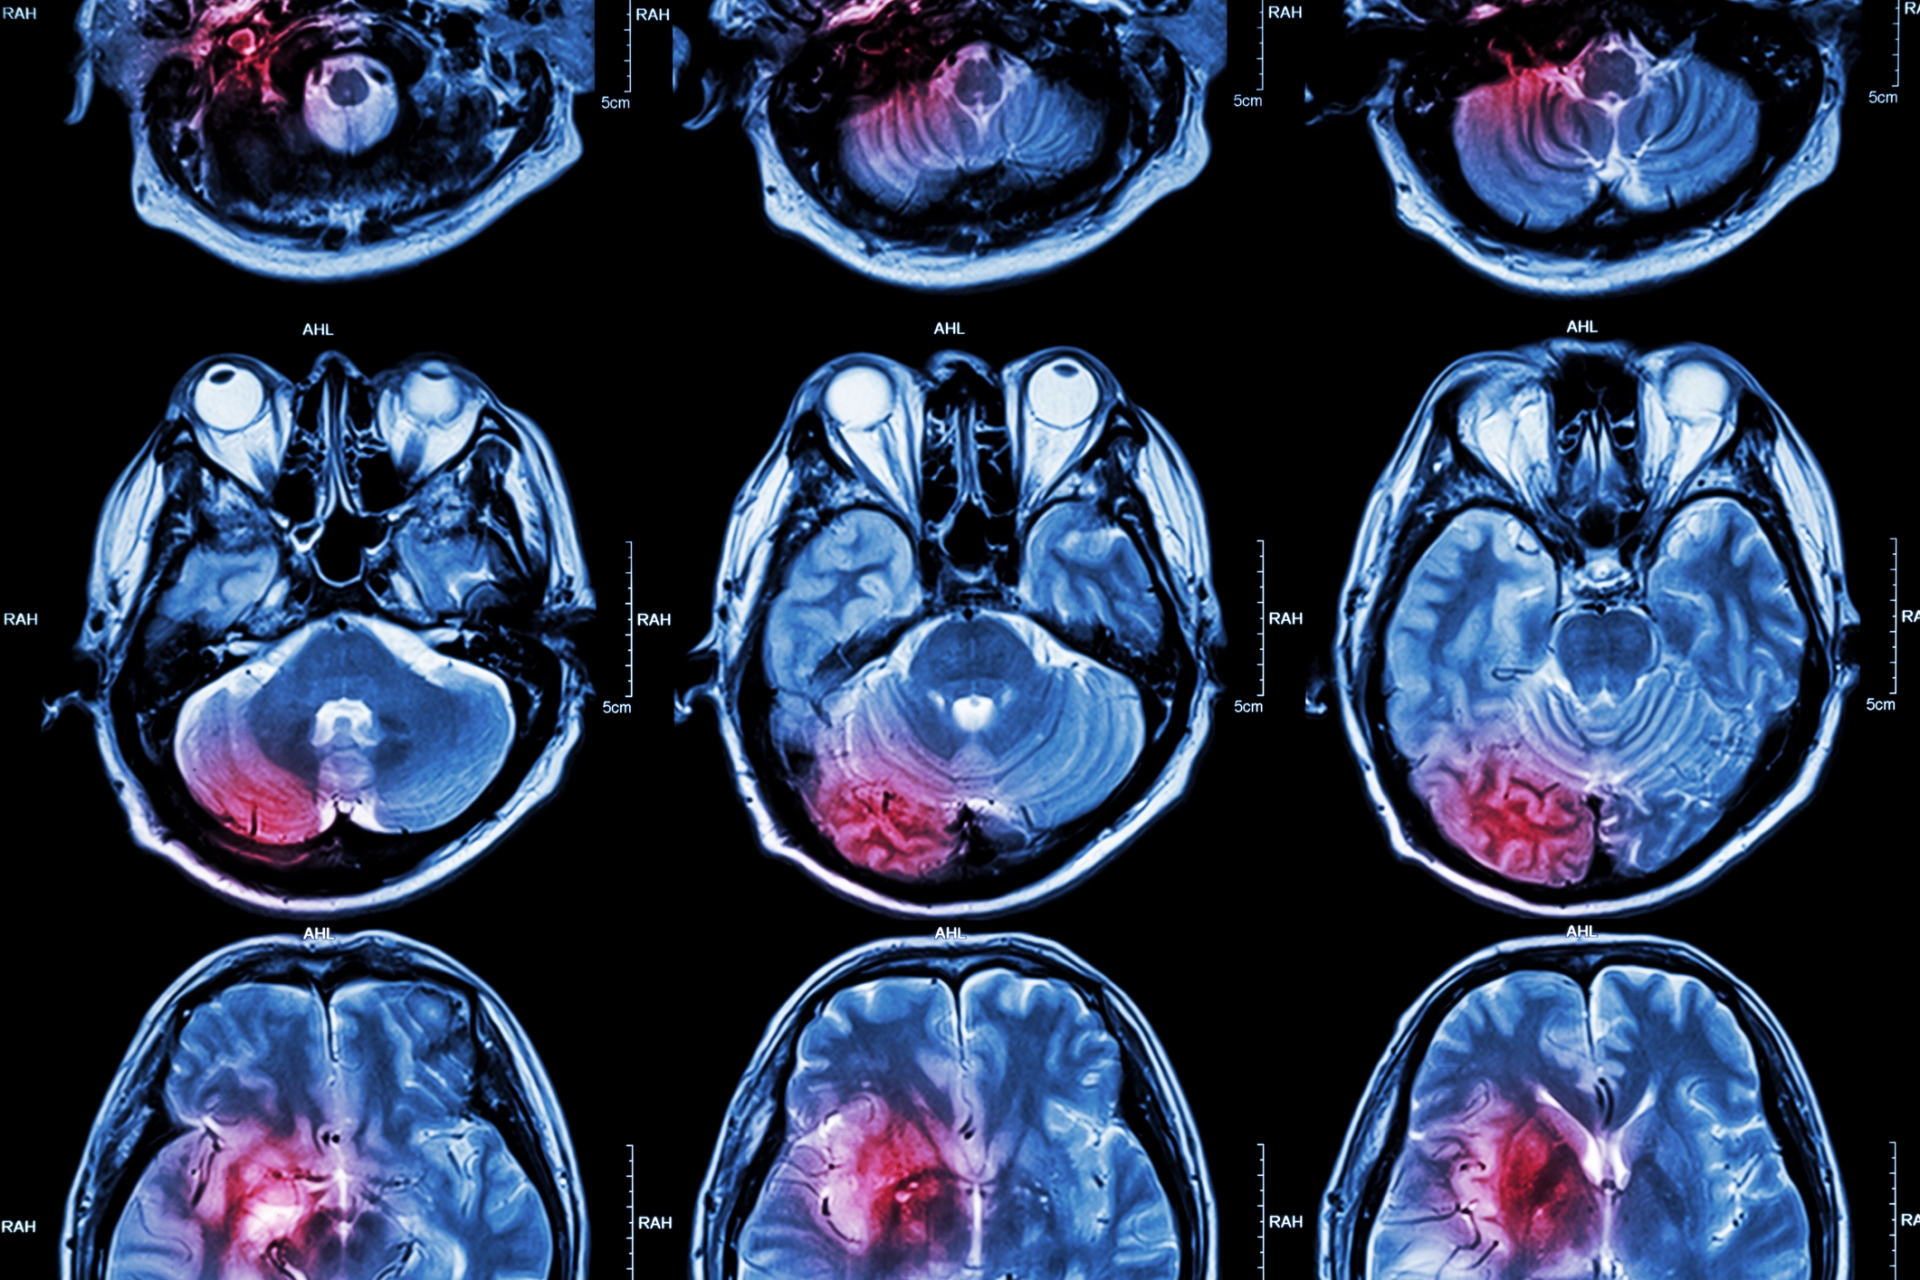

La neurología es el estudio del sistema nervioso y las complejidades del cerebro. Esta especialidad médica está dedicada al diagnóstico, tratamiento y estudio de los trastornos del sistema nervioso, que incluye el cerebro, la médula espinal y los nervios periféricos. El objetivo de esta profesión es mejorar o mantener la función y calidad de vida de las personas.

- Investigación en Neuroimagen: Uso y desarrollo de técnicas avanzadas de imagen para estudiar la estructura y función cerebral.